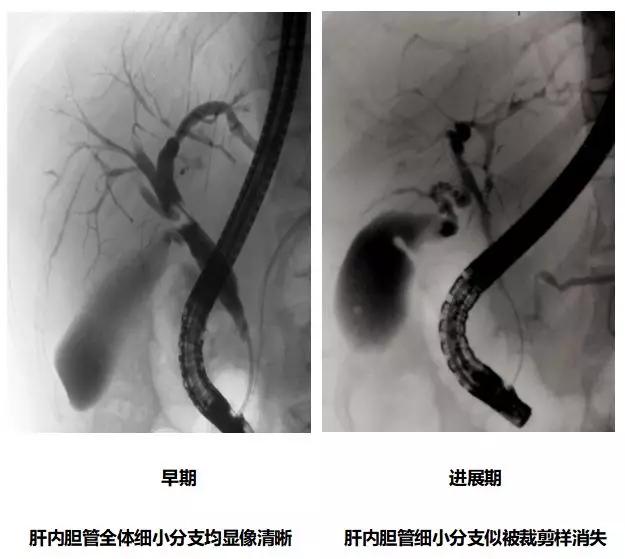

A.胆道影像学检查

ERCP:胆管狭窄与扩张交互,呈串珠状改变

多发短小狭窄,胆管环状受累

PTCD:胆管呈边缘不整羽毛状

ERC:胆管壁呈憩室样突出